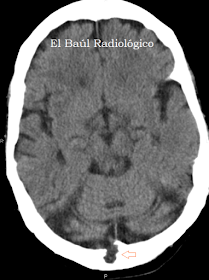

CASO 1)

Varón de 91 años.

FIGURA 1-A) En esta imagen de TC se aprecia una impronta diplóica característica. Comunica con la cavidad craneal y no depende de ninguna vena intracraneal. La localización en el hueso occipital, es muy típica.

FIGURA 1-B) Con ventana de hueso, se aprecia con mayor nitidez. Es polilobulada y de contorno escleroso, lo cual indica crecimiento lento, benigno.